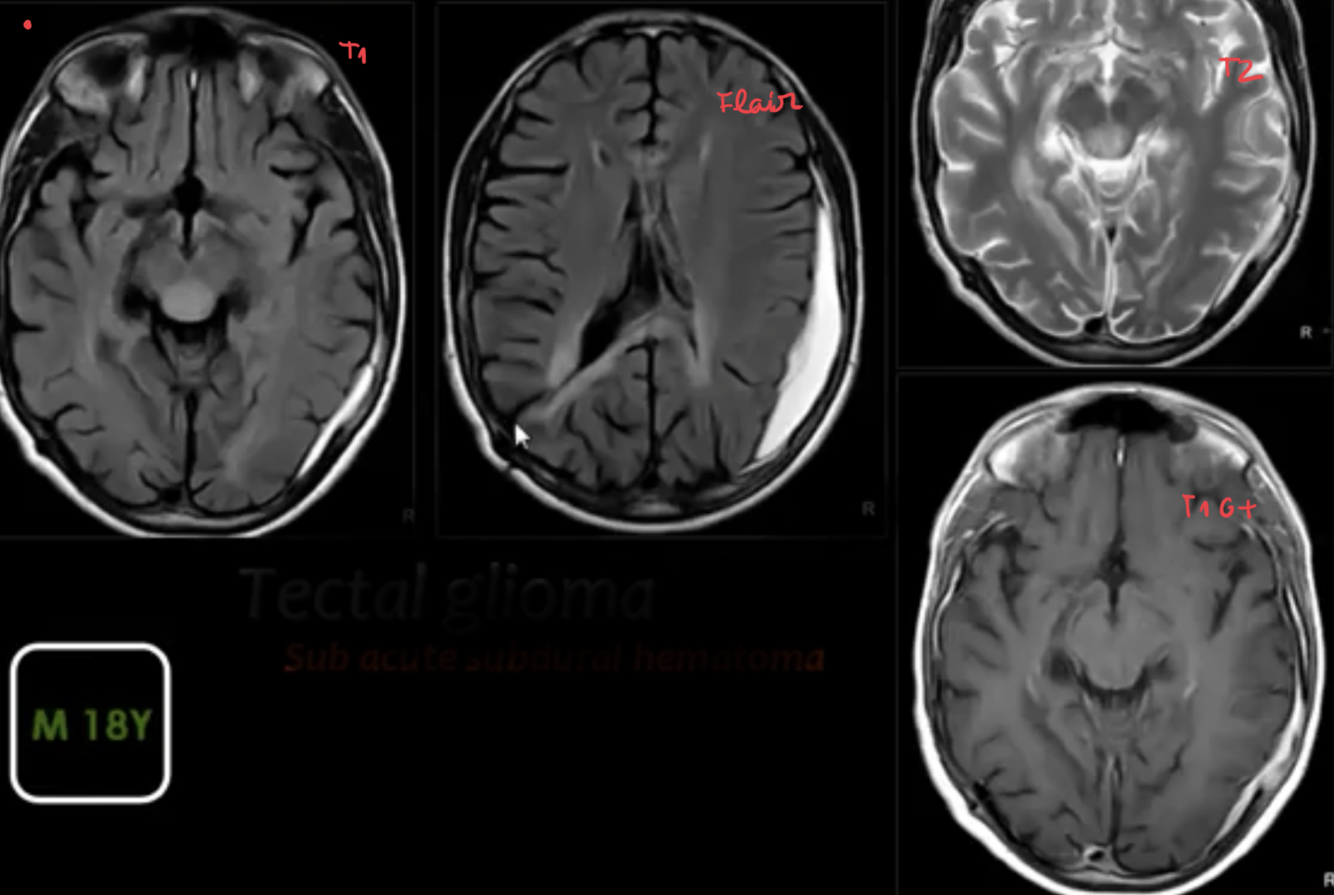

TECTAL GLIOMAS

major points